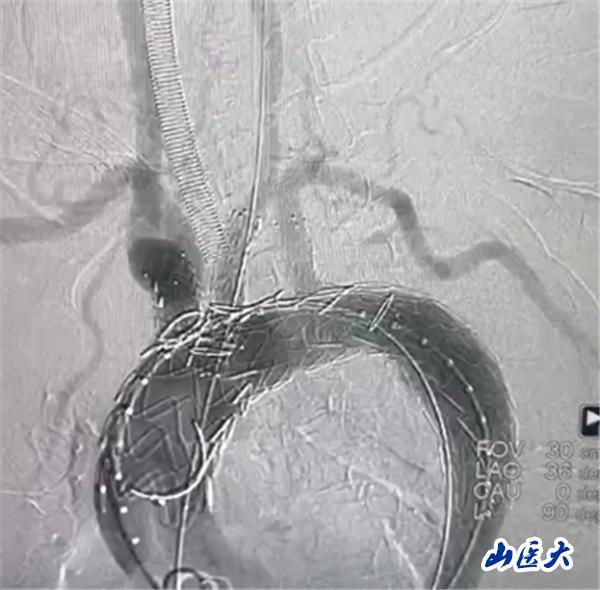

首例患者是一位55岁的女性,她患有高血压约2年时间,平时也会规律服用多种降压药,但血压控制始终不尽人意。2023年4月下午,她出现不明原因的头痛,在家拔罐缓解少许便未到医院就医,次日凌晨突感胸闷、胸背疼痛伴有呼吸困难等症状、家人急忙拨打了120,把患者送入医院急诊科进行救治,医生在急诊科行胸腹主动脉CTA时,显示主动脉弓部-降主动脉及腹主动脉壁间血肿,遂收治入医院血管外科,患者入院10天后复查血肿仍未有改善,依然伴有胸背部疼痛等不适,如不进一步处理,可能发展为夹层危及生命,患者及家属经过与医生团队了解沟通,决定进行创伤小、恢复快的介入手术治疗。张玮教授、符伟国教授、董红霖教授及其血管外科团队(闫盛、常文凯、田琴琴)共同商讨手术方案,最终确定使用Zipper™一体式主动脉弓覆膜支架系统,行胸主动脉覆膜支架腔内隔绝术+无名动脉、左颈总动脉、左锁骨下动脉分支重建术为患者进行治疗。董红霖教授及其血管外科团队根据患者术前头颅CT平扫提示双侧侧脑室旁缺血灶,血压控制不稳定,属夹层壁间血肿非典型夹层等风险点,制定了完整的手术方案,术中经股动脉置入Zipper支架主体,经预留导丝超选无名动脉,并确保主体支架对位准确,顺利置入左颈总动脉、左锁骨下动脉支架,重建弓上三分支。手术过程非常顺利。术后观察主动脉及分支覆膜支架定位准确;无内漏;分支支架通畅,动脉供血正常。

术中造影结果